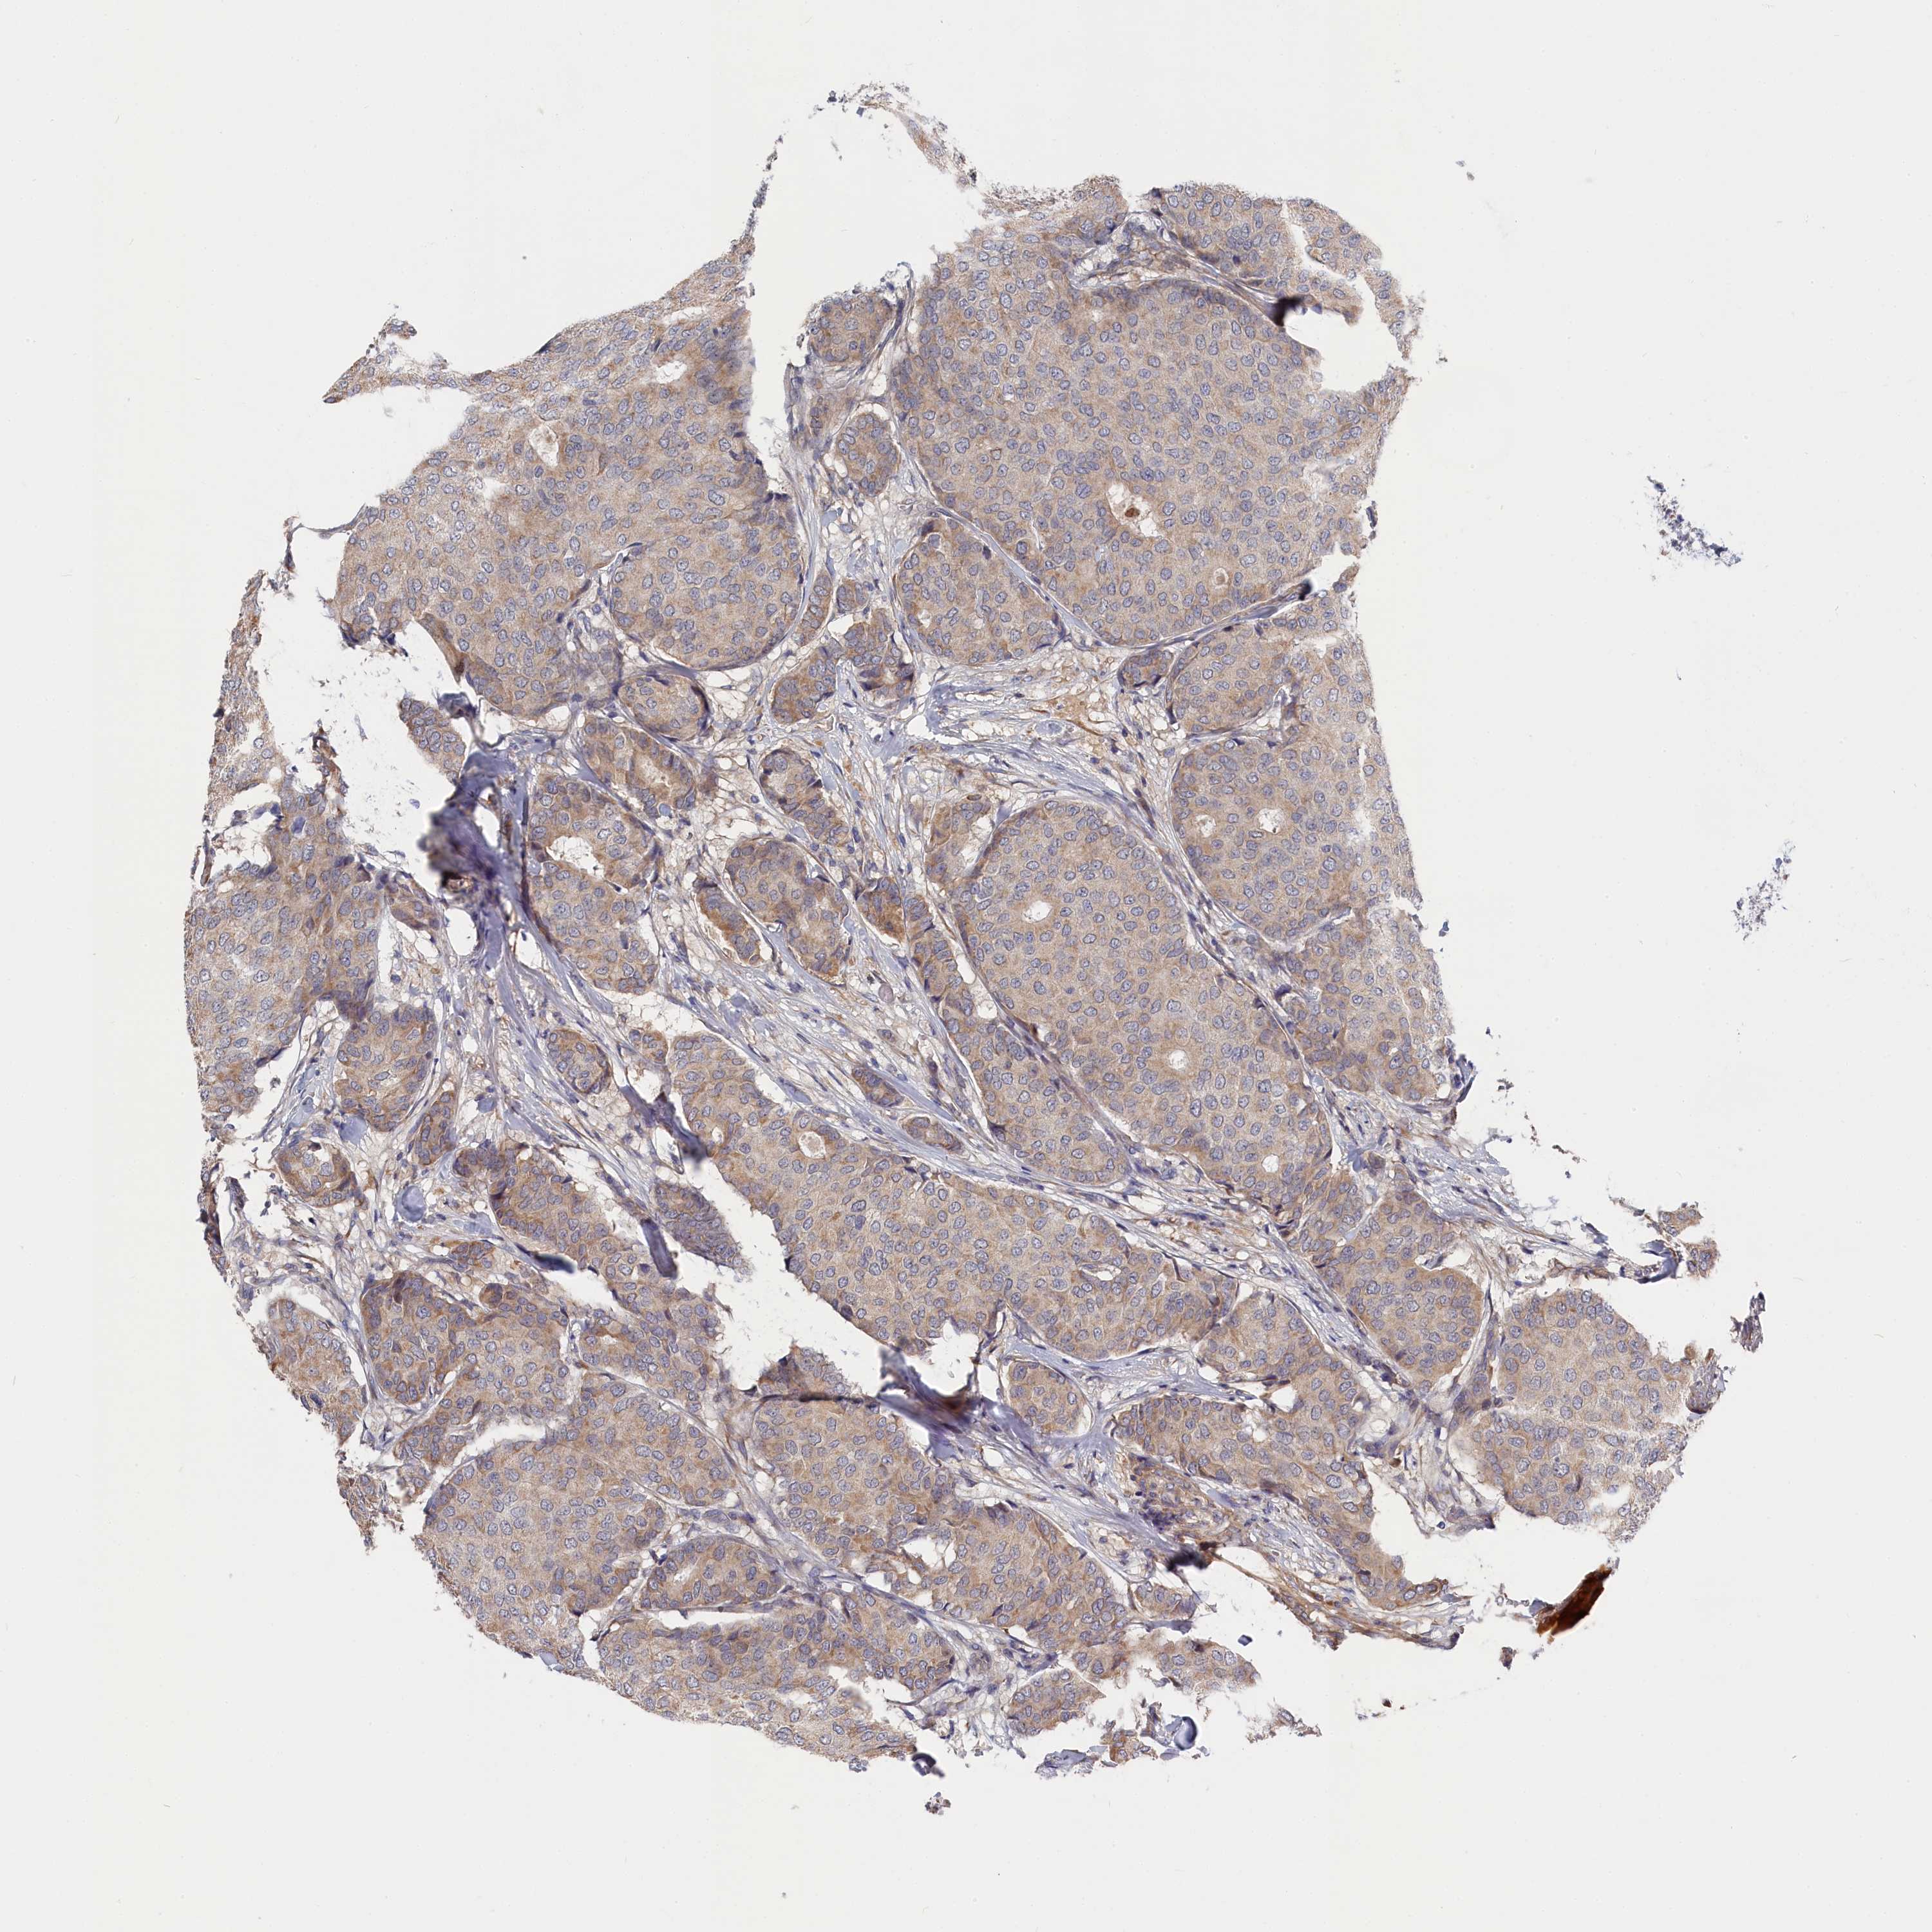

CANCER BREAST CANCER Show tissue menu

BRCA TCGA BRCA VALIDATION PROTEIN EXPRESSION